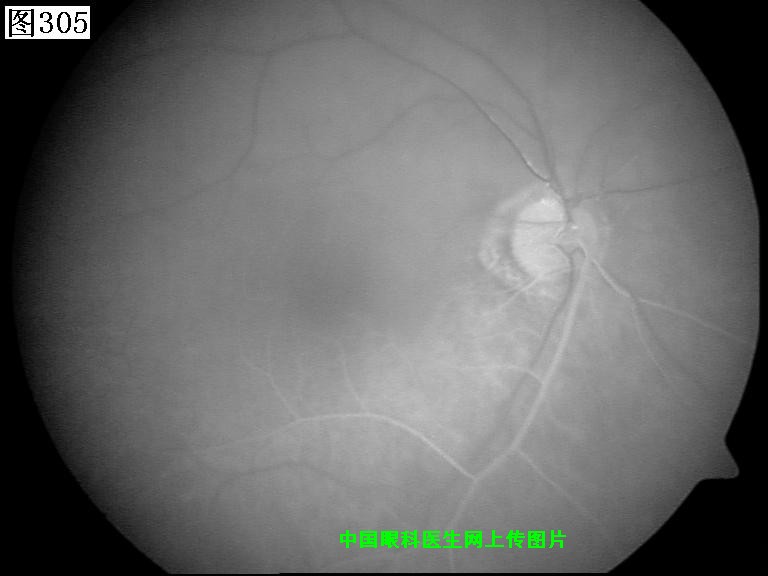

305 306 307 308